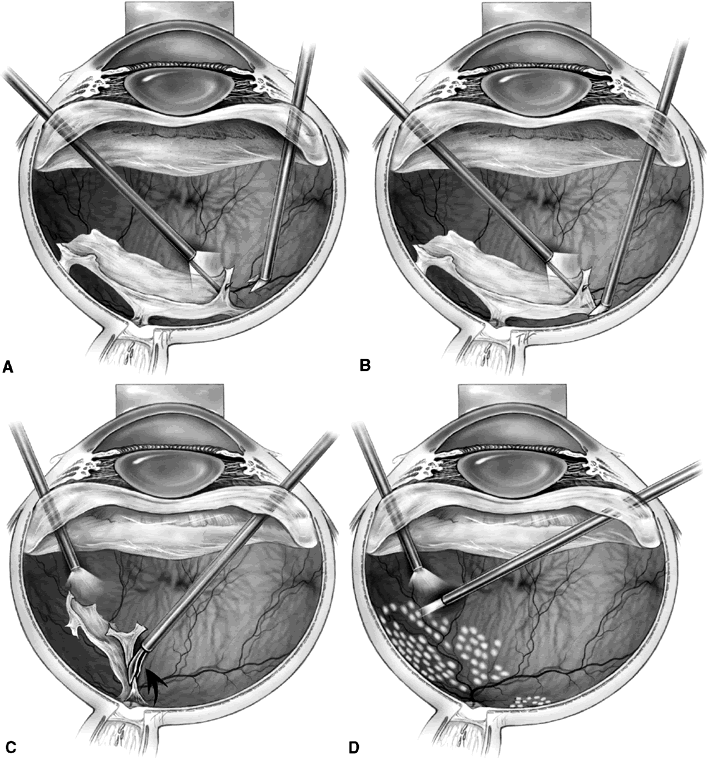

Segmentation was the earliest method used to release retinal traction caused by preretinal fibrovascular proliferation. A core vitrectomy is first performed (Fig. 1A). Anteroposterior traction then is released by circumferentially cutting the posterior vitreous surface around the area of epiretinal proliferation (see Fig. 1B). After the anteroposterior traction has been released and the formed vitreous has been removed, the posterior vitreous surface is cut between epicenters of fibrovascular adhesion, leaving islands of fibrovascular tissue. It also may be necessary to excise bridges of fibrovascular tissue connecting epicenters, using the vitrectomy probe or intraocular scissors (see Fig. 1C). Bleeding often is a problem during segmentation because the neovascular tissue is cut far away from its origin within the retina. Intraocular diathermy often is required to control bleeding from stumps of severed fibrovascular membranes. Raising the intraocular pressure also can be used temporarily to control intraoperative hemorrhage. Finally, panretinal endophotocoagulation is applied (see Fig. 1D).

Fig. 1. A. Core vitrectomy is performed. B. Peripheral vitreous is removed, releasing all anteroposterior traction on the epiretinal membrane. C. The epiretinal membrane is segmented by cutting bridging tissue between foci of fibrovascular adhesion. D. Segmentation has been completed, and panretinal endophotocoagulation is applied.